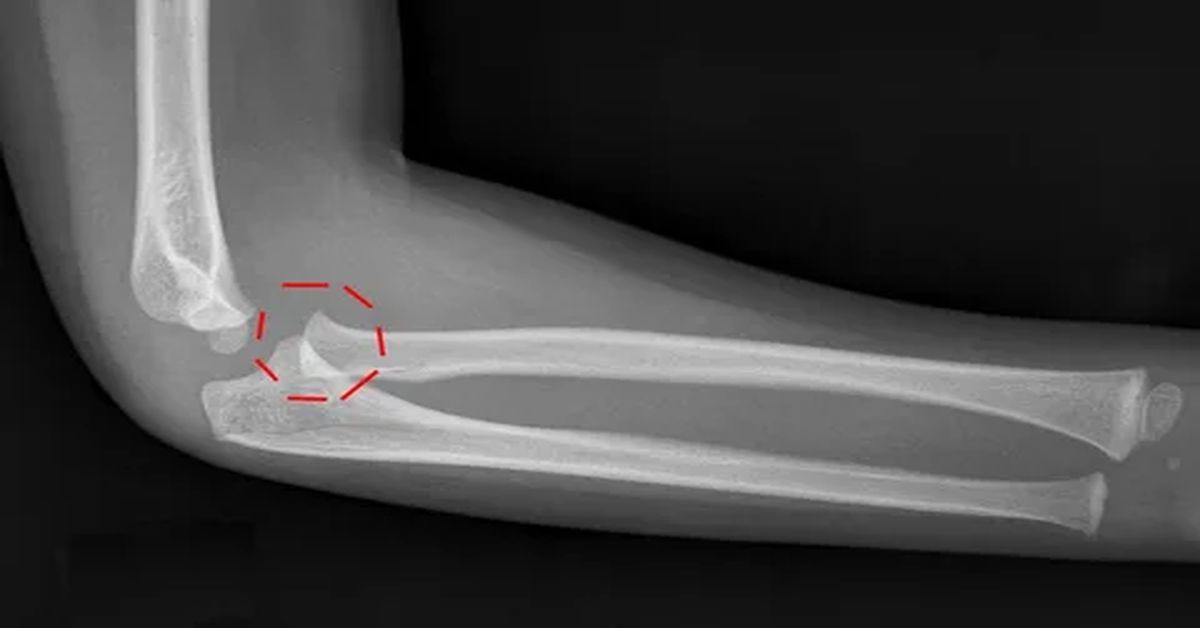

Tedavisinde ilk adım doğru tanı koymaktır. Hastanın şikayetleri ve fizik muayene değerlendirilir. Gerekli durumlarda röntgen gibi görüntüleme yöntemleri kullanılır. Bu sayede eklemin durumu net olarak görülür. Erken tanı, tedavi sürecini kolaylaştırır ve iyileşme süresini kısaltır.